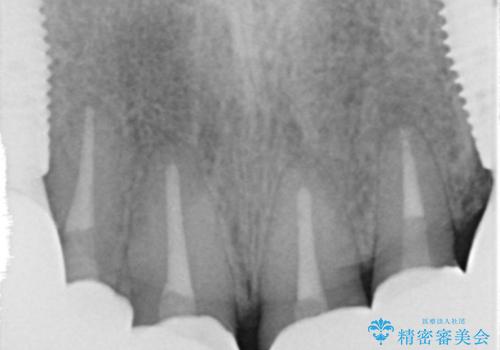

患者様のご希望により、根尖病変の明らかな左上2のみ根管治療を行いました。